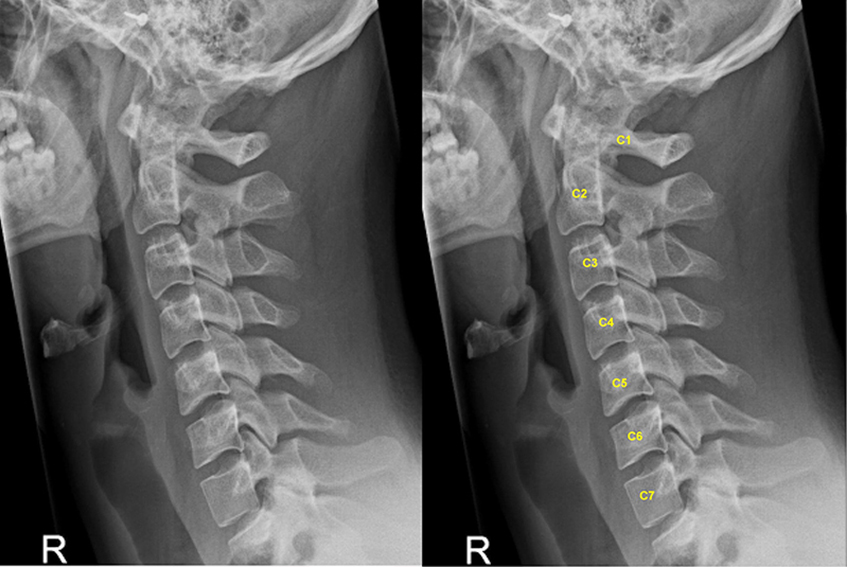

Thoái hóa cột sống cổ

Bệnh lý thoái hóa cột sống cổ khiến sụn khớp và đĩa đệm bị bào mòn, gây chèn ép rễ thần kinh và mạch máu vùng cổ gây nên bệnh lý đau mỏi cổ vai gáy